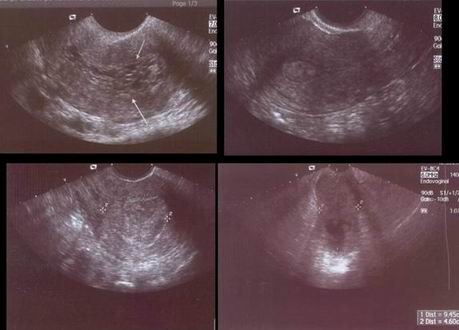

US (základní metoda! – invaze, rozsah!)

Cystoskopie, rektoskopie

CT – při palp. Nebo US podezření na extrauterinní rozšíření, při ascitu

MRI – invaze: senz: 66%, paraaortální LU: jen 8% (málo efektivní!)

obligatorní: gyn.vyš., labor., TV UZ pánve, ledvin, cystoskopie, RTG S+P

fakultatativní: MRI, CT, CA125, IVU